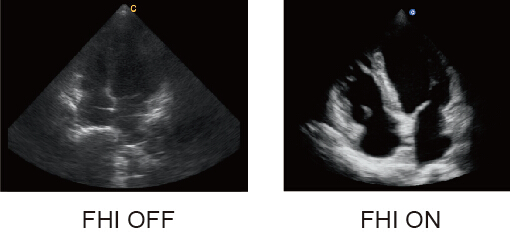

FHI

● Modifica la transmisión y recepción del flujo para maximizar la resolución sin perder la penetración en pacientes de mayor tamaño corporal.

● Mejor que el THI tradicional y el armónico en fase que comprometen la penetración

● La tecnología FHI de Chison mejora las capacidades de diagnóstico en pacientes más grandes, difíciles de diagnosticar.

.jpg)